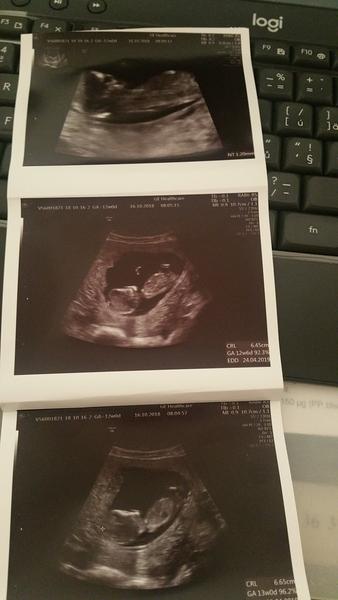

Fotecka z uzv z 12tt. Teraz som 14tt dalsia bude o tyzden 😊